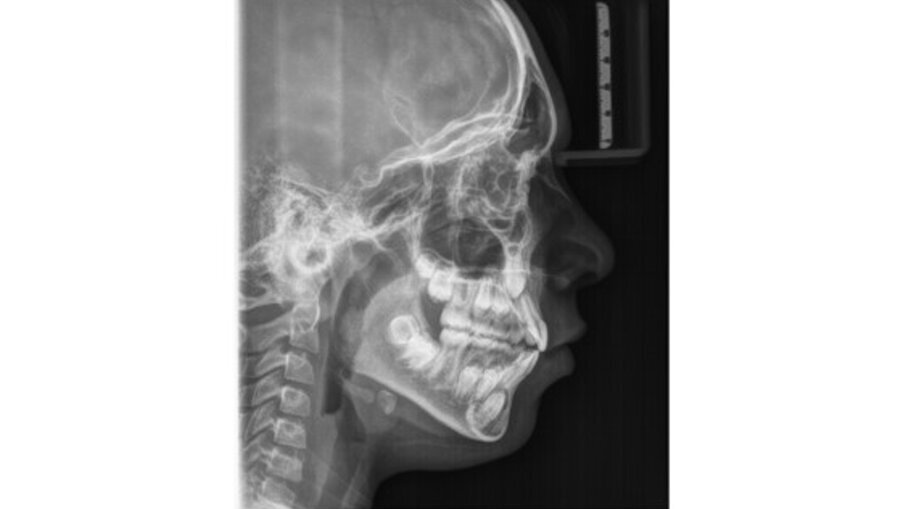

Il paziente, maschio, di 10 anni e mezzo, in dentizione mista. Le arcate dentarie sono in prima classe molare e canina. È presente un overjet di 1 mm e le linee mediane sono centrate. Si osserva un leggero affollamento in entrambe le arcate. Viene raccolta tutta la documentazione clinica per la valutazione del caso ed il successivo trattamento. Si procede alla presa delle impronte per i modelli da studio (Fig. 2). Vengono effettuate l’RX OPT (Fig. 3), la teleradiografia latero-laterale del cranio (Fig. 4) e l’analisi cefalometrica (Fig. 5, Tab. 1). Dopo un anno di terapia intercettiva, è stato eseguito un controllo con una rx OPT per valutare lo stato della permuta dentaria (Fig. 6). All’RX OPT si osserva l’inclusione intraossea con mesio versione dell’elemento 4.3. La CBCT è stata eseguita per valutare la posizione dell’CMI rispetto alle strutture anatomiche vicine (Fig. 7). Il CMI è stato valutato secondo la classificazione di Mupparapu5 nel tipo numero 1. Nella CBCT si osserva parte della corona del 4.3 a contatto con gli apici delle radici degli incisivi inferiori (4.1 e 4.2).

Fig. 4_Radiografia laterale del cranio.